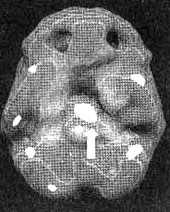

Мозг Мишель. ПМС (до и после)

Трехмерное изображение снизу — активный мозг. На левом снимке состояние мозга за четыре дня до начала менструации. Обратите внимание на повышенную активность в глубокой лимбической системе (см. стрелку).

Мы с коллегами обратили внимание на то, что проблемам в левом полушарии мозга часто соответствует значительная раздражительность, доходящая до насилия. На первом исследовании мы обнаружили у Мишель сильно выраженное повышение активности в зоне, расположенной рядом с центром мозга, в глубокой лимбической системе (отвечающей за наше настроение), преимущественно с левой стороны. Такое состояние, отмечающееся преимущественно в одной, а не в обеих частях мозга, часто соответствует циклически проявляющейся склонности к депрессии и раздражительности. Результаты второго исследования, проведенного ближе к середине цикла, кардинально отличались от предыдущих. Глубокая лимбическая система была без изменений.

Что бы ни говорили некоторые спорщики, ПМС, или предменструальный синдром, на самом деле существует. Женщины с ПМС ничего не придумывают. Химия их мозга действительно изменяется, в результате чего он выдает реакции, с которыми они не могут справиться. В глубокой лимбической системе находится больше рецепторов эстрогена, чем в прочих областях мозга. Поэтому у некоторых женщин эта зона более чувствительна к изменениям уровня эстрогена, которые отмечаются во время полового созревания, перед началом цикла, после рождения ребенка или во время менопаузы. Иногда эти колебания производят, без преувеличения, драматический эффект. Для типа женщин, к которому относится и Мишель, ПМС может оказаться не просто болезненным состоянием, но и попросту опасным. Именно поэтому на ПМС следует обращать внимание. Нечто подобное я наблюдал и у других пар. Во время наиболее безмятежного периода ее менструального цикла семейные отношения у нее прекрасные. В самый трудный период цикла в семье начинаются скандалы и взаимное отчуждение.